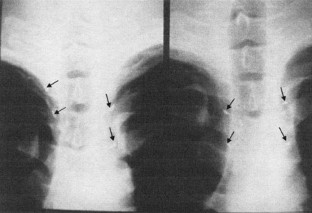

A total of 114 patients with various sympathetic disorders underwent endoscopic sympathetic block over different thoracic ganglions by the clipping method. The advantages of this method include the recognition of the clipped level, changeability, and reversibility. However, 4.4% of patients were unilaterally clipped at the wrong level.

Fig. 1

Fig. 2

Fig. 3